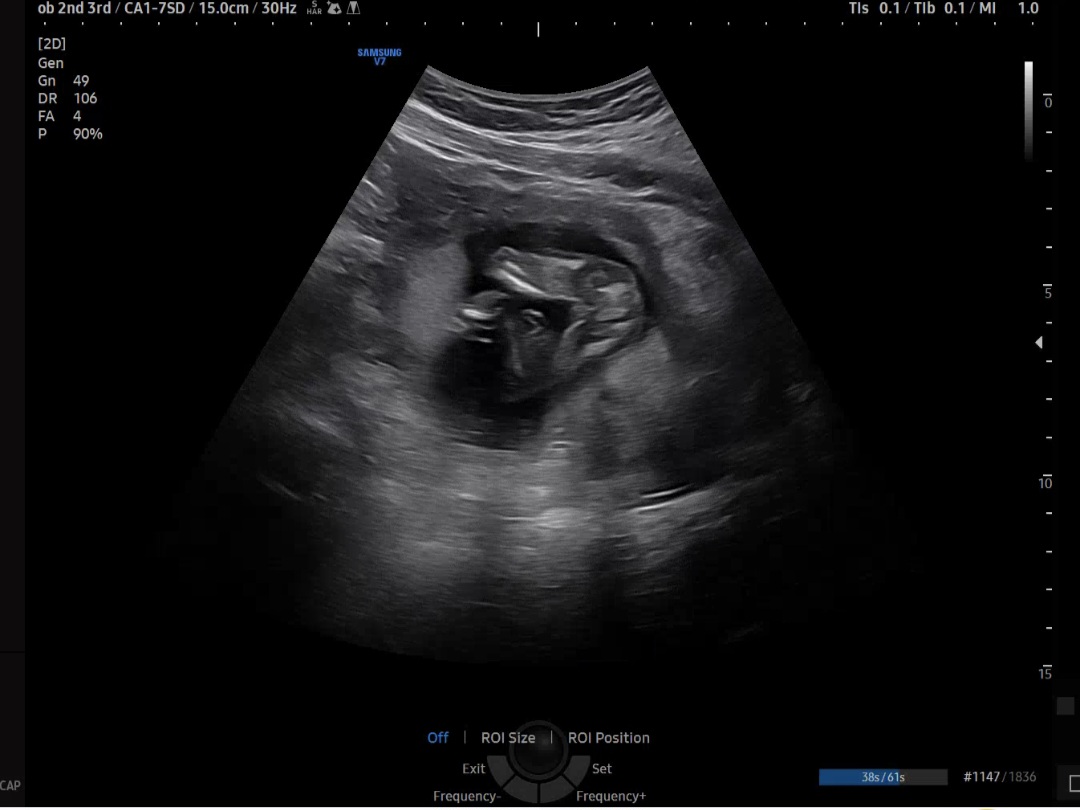

16주 성별이용

의사선생님이 "딸 같네요~"하시긴 하셨는데 20주차 쯤에 확정된다고 해서요. 딸로 믿어도 될까용...? 의사쌤 말을 못 믿는거보다 시어머님께서 딸을 너무 원하셔서 하루 빨리 젠더리빌 하려고요!!